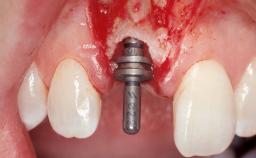

Late Flapless Placement of an Implant in a Maxillary Left Central Incisor Site

A 39-year-old male patient presented with a chief complaint of discomfort and gingival discoloration around his maxillary left central incisor. He was in good general health and was a non-smoker. His past dental history was significant because of the traumatic fracture of tooth 21 in a sporting accident at age 13. Initial dental treatment included endodontic therapy and a full-coverage restoration. The patient became symptomatic 5 years later, when structural failure of the tooth resulted in the dislodgment of the crown. Endodontic retreatment, apical surgery, and post-and-core restoration were performed.

Placement Protocol Early or late implant placement

Bone Volume Deficient horizontally, requiring prior grafting

Esthetic Risk High